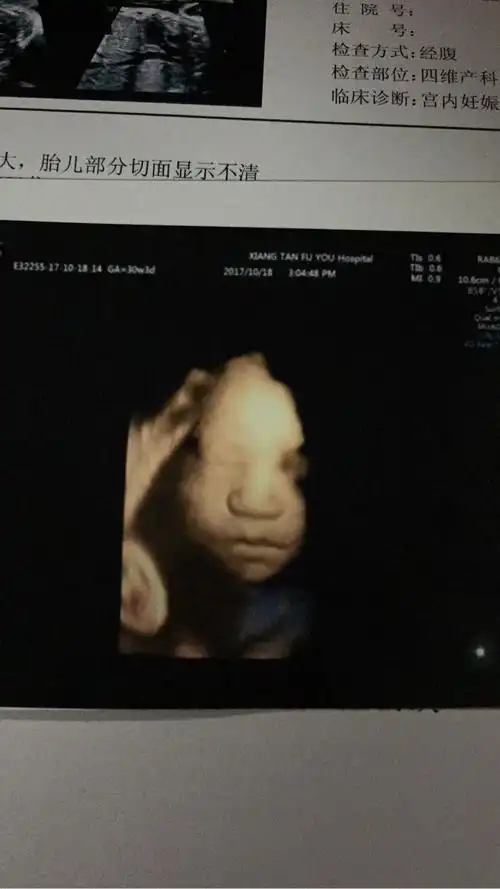

四维拍出来,当时一看好丑啊,这鼻子也太大了,我的显性基因也太强了

四维出来的时候发照片给我姐,她说怎么看着这么丑啊,真的很丑吗?

孕妈做b超发现娃嘴歪了,医生安慰说正常,宝宝出生后妈妈被丑哭

为什么胎儿四维照"丑相"?b超医生告诉你真相,原因是这三点